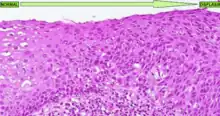

La forma más conocida de displasia es la displasia cervical, bastante común en las lesiones precursoras del cáncer de cuello de útero. Es un tipo de displasia que tiene como causa etiológica el papillomavirus humano y que afecta al cérvix uterino de las mujeres. En este tipo de displasia se observa una diferenciación muy clara del tejido cervical dañado respecto al tejido sano (ver imagen adjunta). En esta enfermedad hay tres grados de displasia diferentes:

- Universidad de Utah, Escuela de Medicina. Imagen de una displasia de cuello uterino; Displasia cervical escamosa de mayor magnificación Descripción en inglés. Último acceso 5 de marzo de 2008.